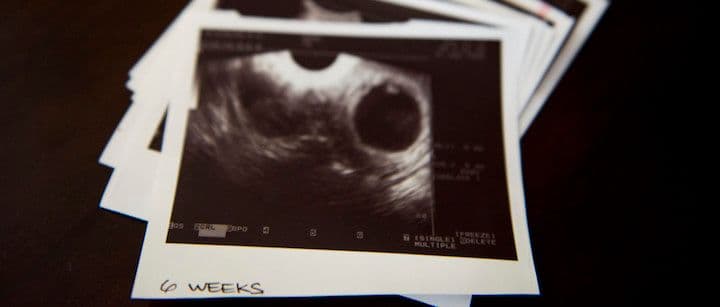

Your body goes through many changes throughout the first trimester, as does your baby. Even in the first few weeks after conception, the fetus begins growing at a rapid pace, magically transforming from a beating heart and formed organs to developing arms, legs, and facial features. Here are some things that will happen as your baby goes through the first 12 weeks of life.

Your baby will go through a lot of changes and developments during the first few weeks of pregnancy. Keep in mind that developments happen to start in week 1, though you won’t know you are pregnant until around week 3-4. During the first month of pregnancy, your baby is about 7mm long, which is roughly the size of a grain of rice. The baby is protected by the amniotic sac and begins forming its major organs and body systems. The heart will beat in the first month, the eyes and ears begin to develop, and the fetus will have limb buds that eventually become its arms and legs.